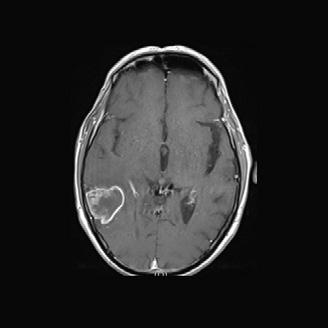

Dr Ben Newland Multifocal GBM on brain scan

The £500,000 award will fund a project being led by Dr Ben Newland at Cardiff University to design a unique sponge-like gel to be inserted into the space left following surgery to remove GBM tumours.

The ‘super sponge’ will deliver combinations of repurposed cancer therapeutics, which are unable to pass through the blood-brain barrier, directly to the site. Not only will this novel technique reduce the effects of drugs on non-targeted areas, but it will also deliver effective treatment to the tumour cells which are left behind after surgery and go on to cause recurrence of the disease.

Innovative research to develop a set of ‘super sponges’ to deliver drugs directly to the brain following surgery for glioblastoma (GBM) is being funded thanks to a partnership between Brain Tumour Research and the Medical Research Council (MRC).